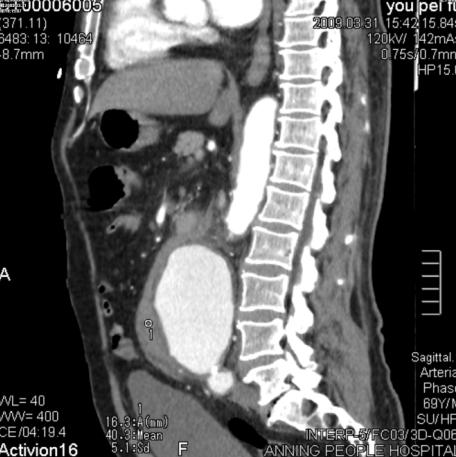

增强后:腹主动脉下段至左右髂总动脉上端明显扩张,最宽处约6.8cm,上下径约为13cm,成瘤样改变,边界清楚,形态规整。

1.腹主动脉瘤。(腹主动脉下段至左右髂总动脉上端)

3.右肾周及腹主动脉周围,中上腹腔见条带状及片状稍低密度影(多考虑腹腔包裹性积液,请结合临床病史。